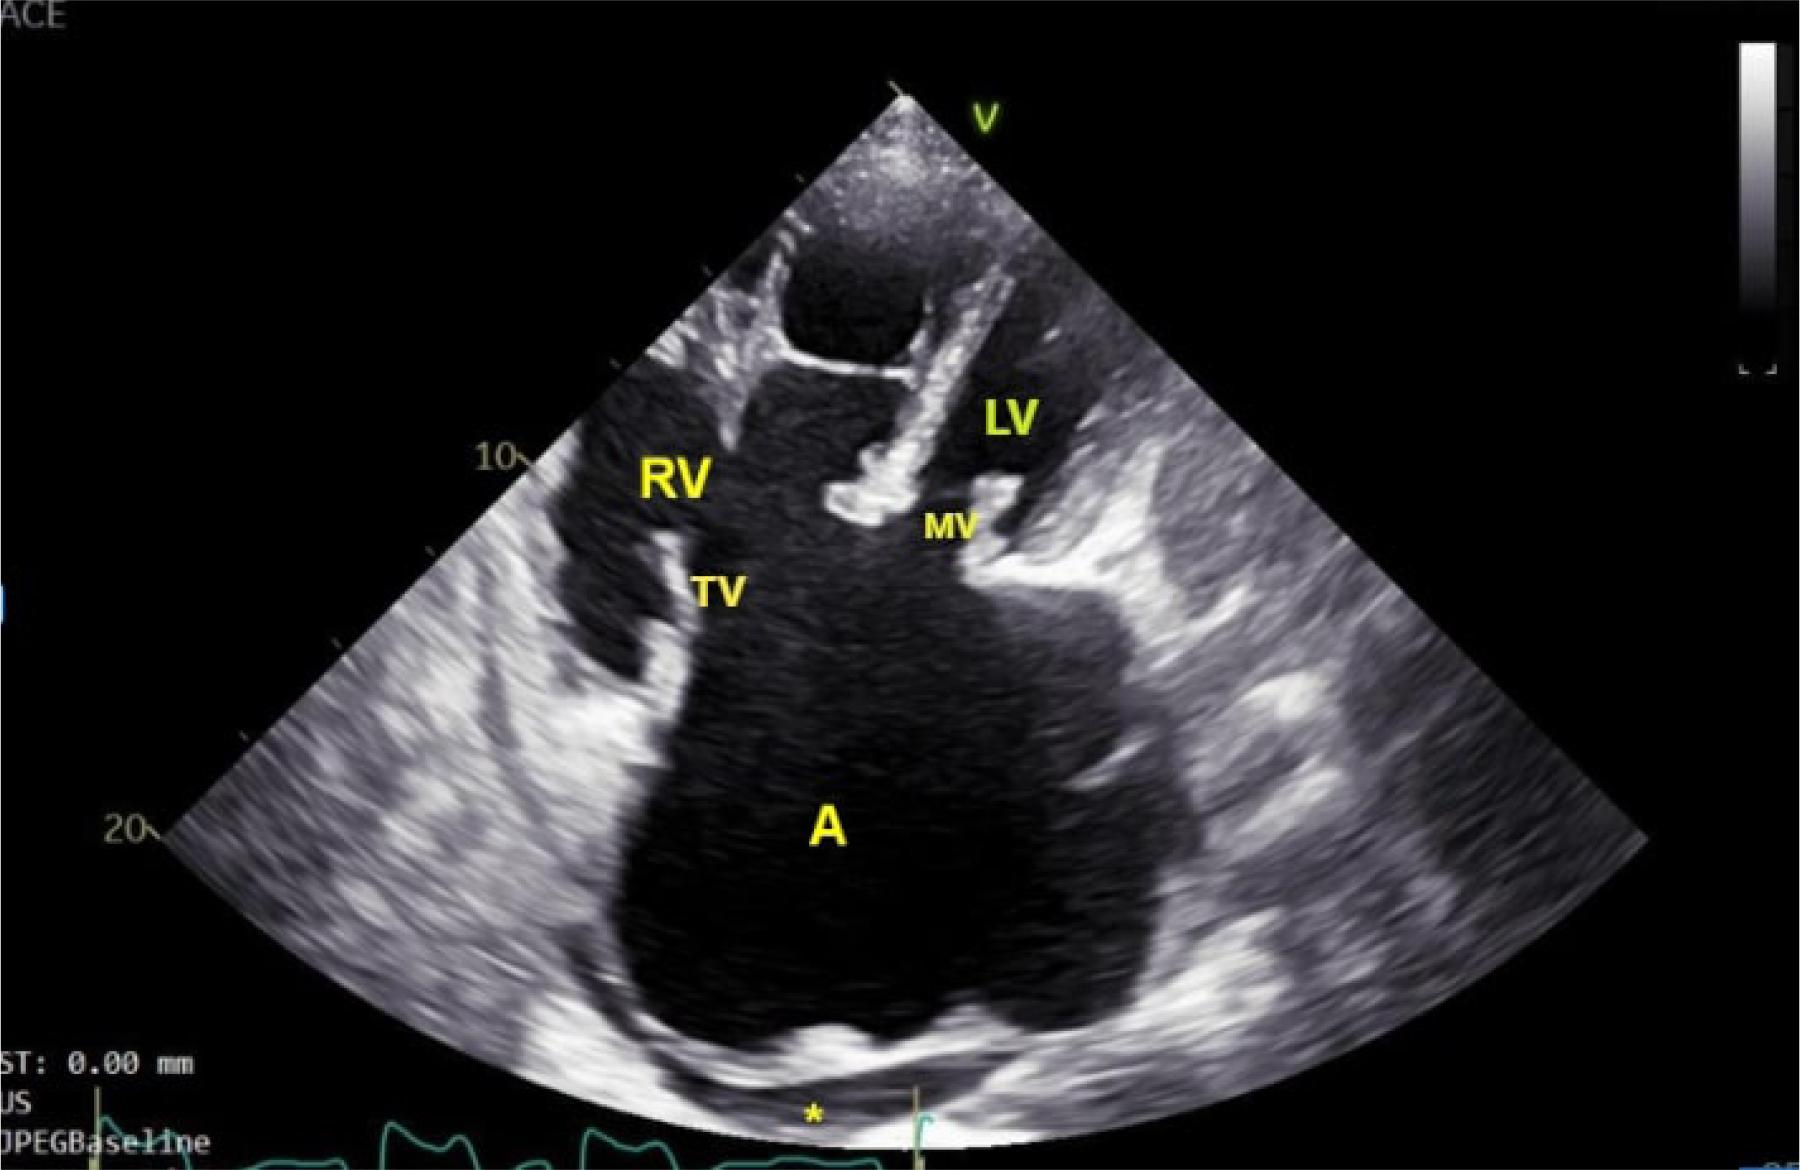

A more detailed echocardiographic evaluation was repeated and revealed a single atrium with a volume of 530 ml, severe mitral regurgitation, severe tricuspid regurgitation, perimembranous VSD with bidirectional flow on Doppler interrogation, left ventricular (LV) end-diastolic volume of 92 mL and end-systolic volume of 33 mL, LV ejection fraction of 60%, right ventricular (RV) basal/longitudinal/medium diameters of 71/89/80 mm, RV longitudinal systolic dysfunction (suggested by the tricuspid annulus plane systolic excursion of 11 mm), estimated pulmonary artery systolic pressure of 92 mmHg, Qp:Qs=3.89, dilated inferior vena cava, mild pulmonary regurgitation, and moderate pericardial effusion (Figure 2–3, video 1-2).

Transthoracic echocardiography modified apical 4-chambers view: large single atrium (A), dilated right ventricle (RV), small pericardial fluid (*), left ventricle (LV), mitral valve (MV), tricuspid valve (TV).